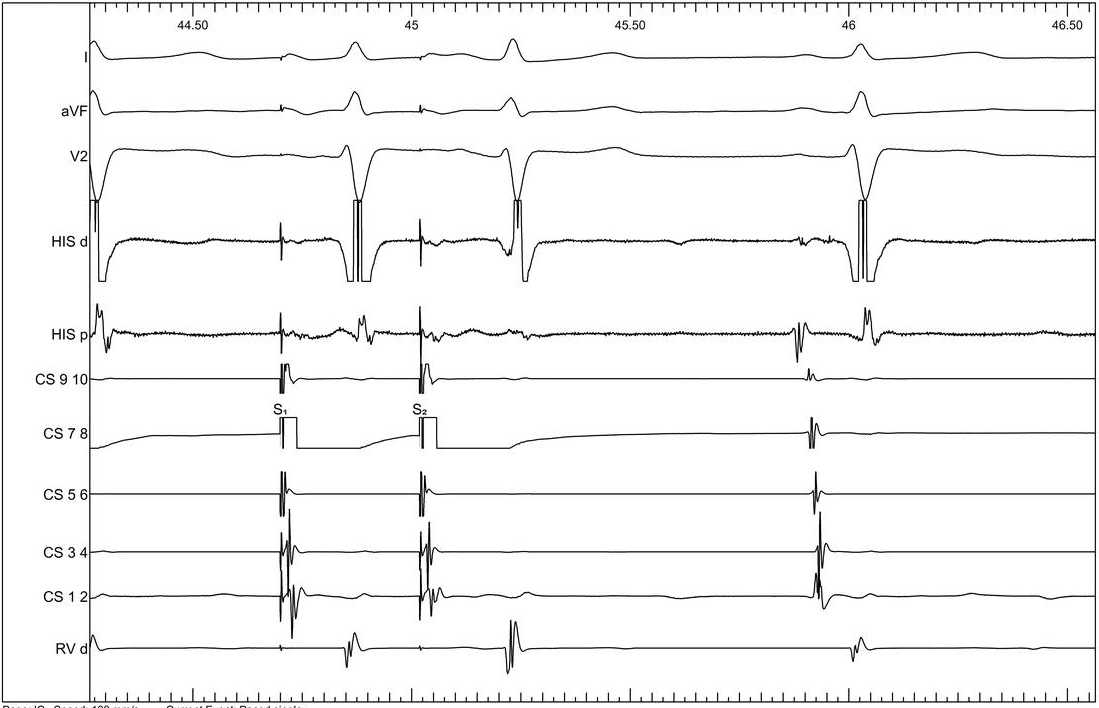

Atrial extrastimulus 600/320

04_cs_600_320.jpg